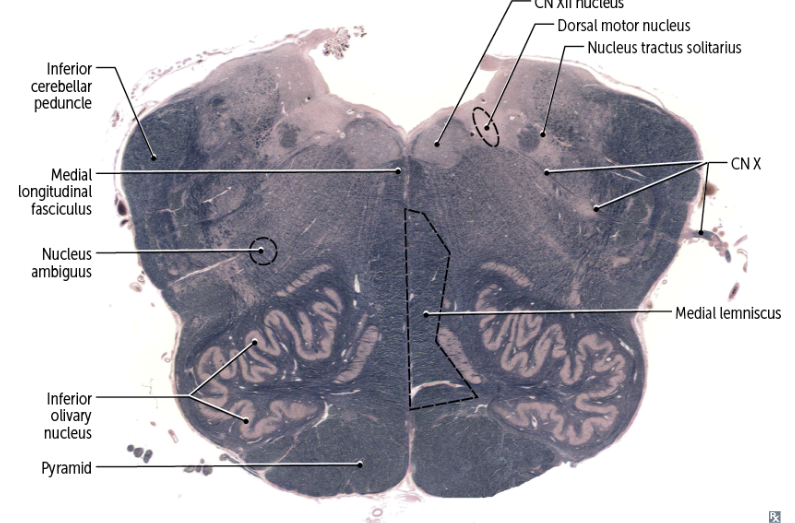

recognizable features of the MEDULLA in cross-section

A

-anterior/ventral: medullary pyramids & inferior olive

-posterior/dorsal: 4th ventricle CLOSES and gives way to the raised tubercle in the midline of the hypoglossal nerve